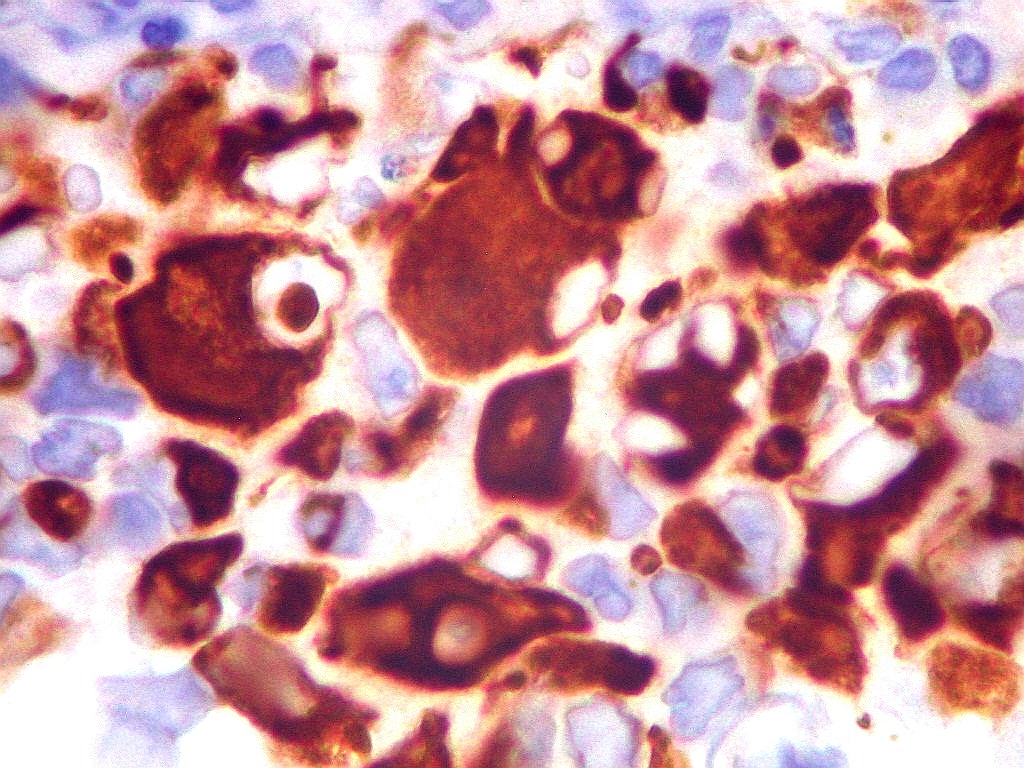

| EMA. Antígeno epitelial de membrana. Ocorre em epitélios, e também em células meningoteliais. Aqui fortemente positiva nas células deste tumor teratóide rabdóide atípico. Negativo no folículo linfóide incluído fortuitamente na amostra. Positivo também no epêndima do III ventrículo adjacente ao tumor. Notar que as células ependimárias são ciliadas. |